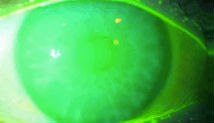

淚膜破裂時間測定:

1、角膜熒光素納染色

2、計算淚膜破裂時間